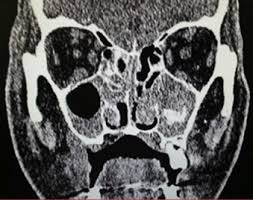

| Rhino cerebral Mucormycosis at the upper jaw |

Rhino cerebral

Mucormycosis is a type of Mucormycosis affects the Sinuses, Nasal cavity, and

brain.

Symptoms of

Rhino cerebral Mucormycosis; one-sided face swelling, Headache, Nasal or sinus

congestion, black spots inside the mouth at upper jaw, and Fever.